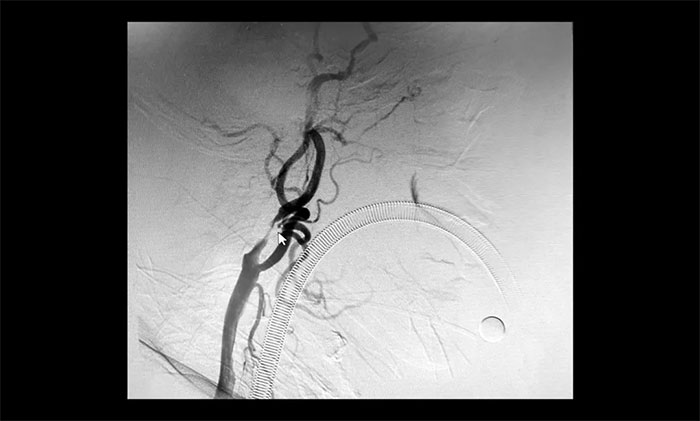

在明確告知分期手術(shù)方案,并取得患者家屬同意后,5月21日,于耀宇主任和團(tuán)隊(duì)醫(yī)生在全麻下為曹老伯先行腦血管造影術(shù)+左側(cè)頸內(nèi)動(dòng)脈支架經(jīng)皮置入術(shù),術(shù)后給予預(yù)防感染、護(hù)胃、補(bǔ)液等對(duì)癥治療。

▲ 術(shù)后,左側(cè)頸內(nèi)動(dòng)脈狹窄明顯改善